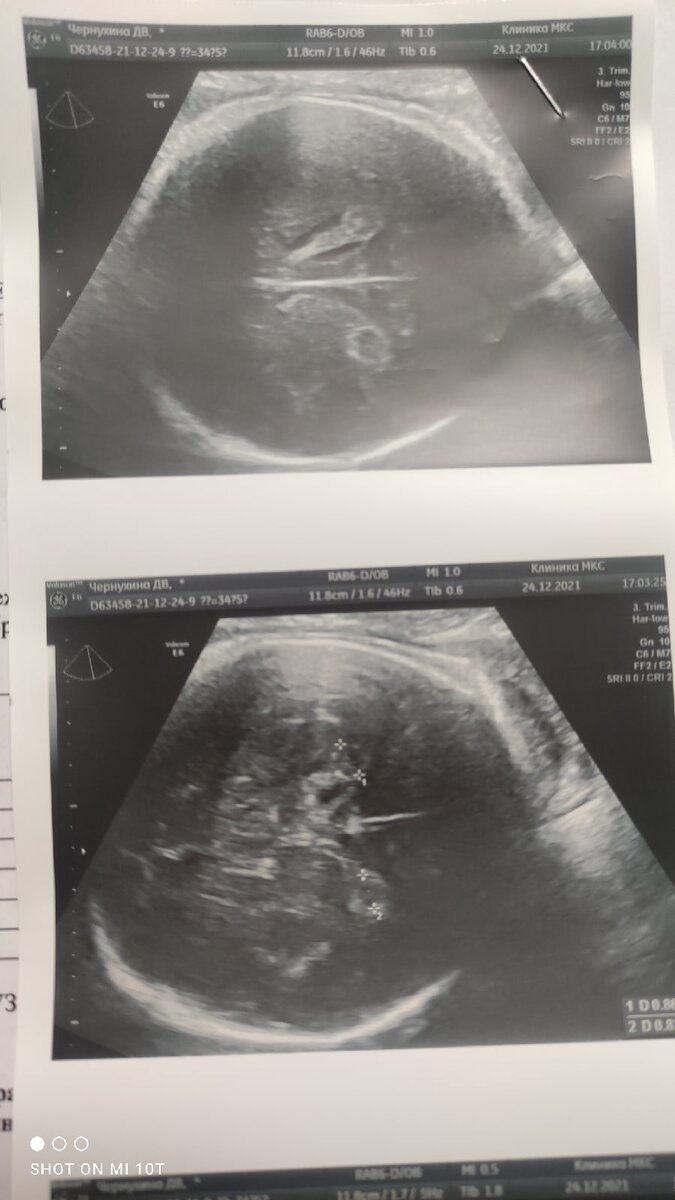

УЗИ со второго скрининга

Обычно кисты видят на первом или втором скрининге, и к третьему они чаще всего рассасываются. По крайней мере, так мне объясняли врачи. В нашем же случае все было наоборот. Первый и второй скрининг были идеальными. А вот на третьем нашли кисты. Две штуки. Достаточно большие - почти по 1 см каждая.

Кисты ГМ